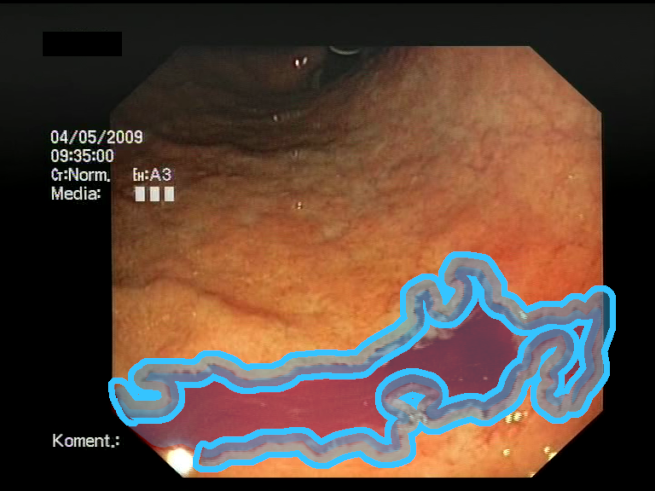

As a result of the design process, nine high-level features (denoted F1–F9) were defined. The features are proposed with simple definitions that also include exemplary images, presented in Table 1. For each image, a blue annotation is presented, illustrating the image regions where the feature is hypothetically present.

Table 1.

Definitions of the nine proposed visual features of endoscopic bleeding. For each image, a blue annotation is presented, which illustrates the area of the image where the feature is hypothetically present.